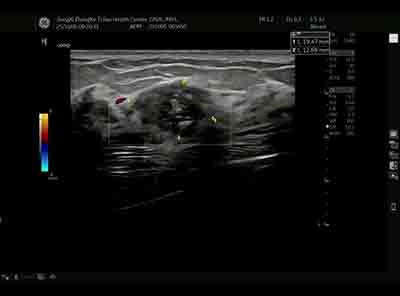

血流模式的精細評估 乳腺良惡性腫瘤的血流特征存在顯著差異。E11采用的超微細血流成像技術具有突破性意義:

準確區分腫瘤邊緣與內部血流分布 惡性腫塊通常表現為血流豐富、走行紊亂、動靜脈瘺形成,而良性病變血流相對稀疏、走行規則。這種差異為鑒別診斷提供了重要參考。